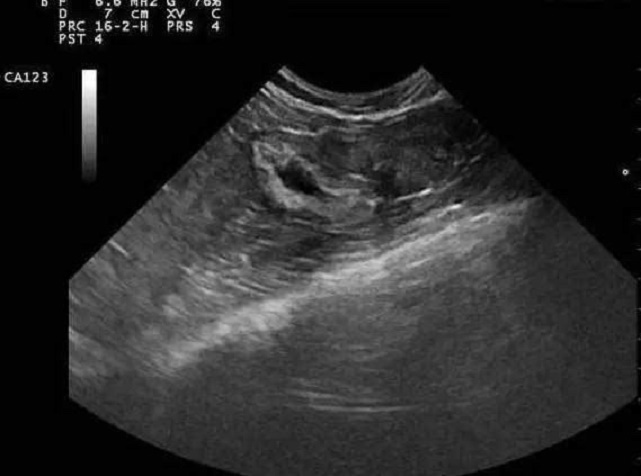

到了医院说明情况之后,医生带着小含做了B超一看,说不用清宫,因为还有一个活胎。这是怎么回事呢?原来,医生告知,小含怀的是双胞胎,一个没有保住,但是另外一个活了下来。全家一听,高兴坏了。